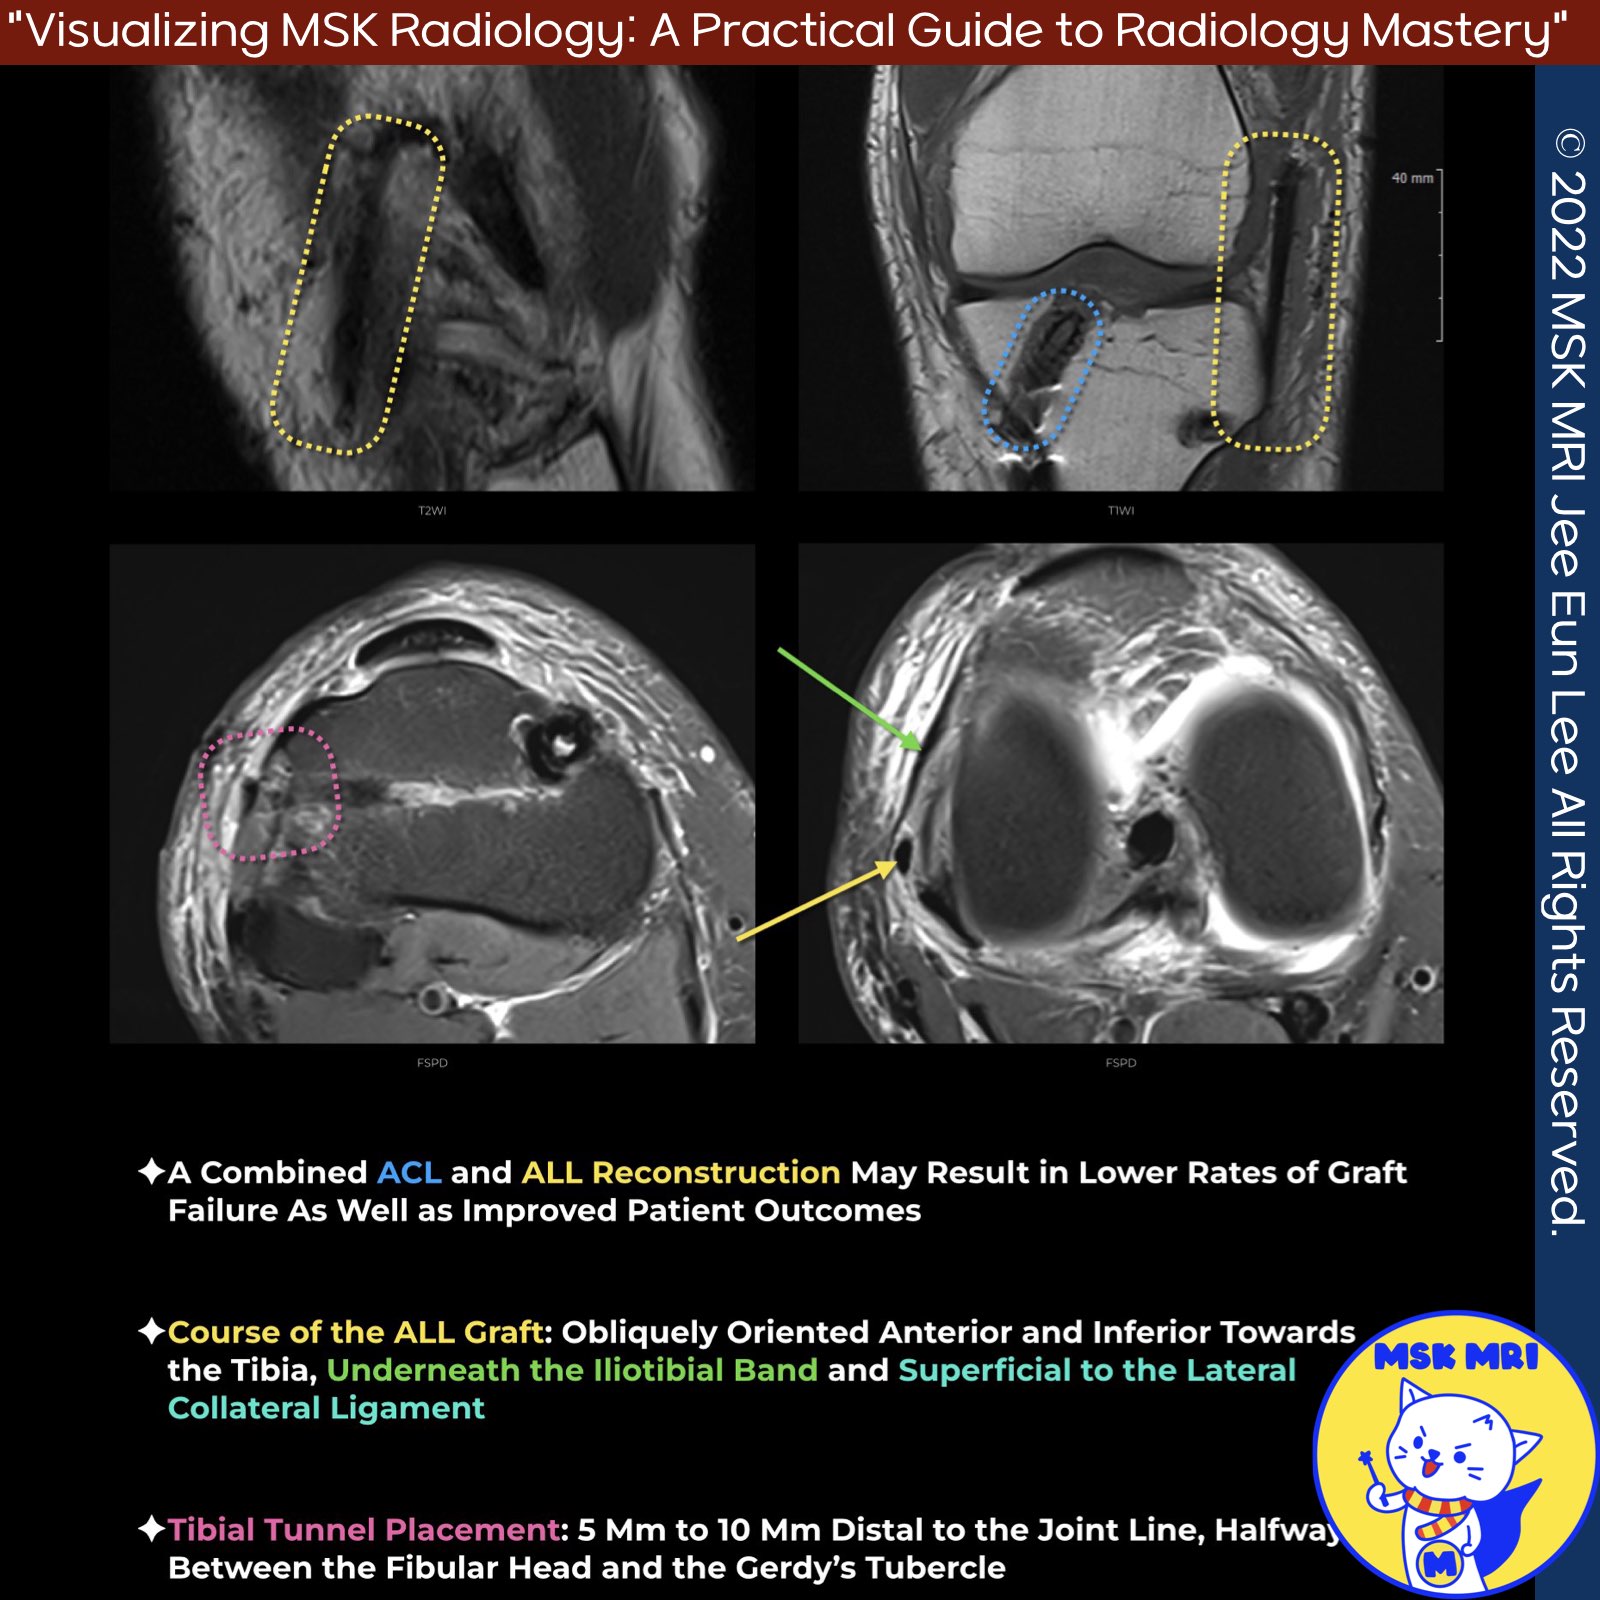

📌Anterolateral Ligament (ALL) Reconstruction

- The Anterolateral Ligament (ALL) is an important secondary stabilizer that resists excessive internal rotation and anterior tibial translation.

- Combined ACL and ALL reconstruction may lead to lower graft failure rates and improved patient outcomes.

- Femoral tunnel: Slightly posterior and proximal (4mm posterior, 8mm proximal) to the lateral femoral epicondyle

- Tibial tunnel: Approximately 5-10mm distal to the joint line, halfway between the fibular head and Gerdy's tubercle

- ALL graft follows the anatomical oblique course, anterior and inferior towards the tibia, through a soft tissue tunnel underneath the iliotibial band (ITB) and superficial to the lateral collateral ligament (LCL)